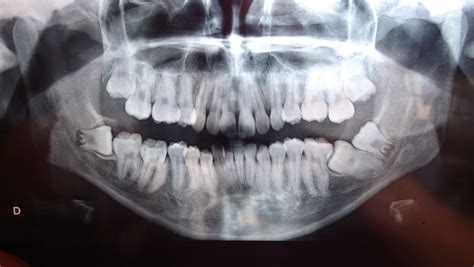

La extracción del tercer molar, también conocida como muela del juicio, es un procedimiento quirúrgico frecuente en odontología. Tanto el dentista general como el cirujano maxilofacial deben estar familiarizados con todas las posibles complicaciones que pueden surgir.

Las complicaciones habituales de la cirugía del tercer molar son bien conocidas y suelen explicarse detalladamente a los pacientes durante la obtención del consentimiento informado. Esta revisión sistemática pretende servir como recordatorio de las complicaciones poco habituales que pueden presentarse en este procedimiento rutinario.

Las complicaciones más conocidas y frecuentes fueron la lesión permanente nerviosa y las fracturas mandibulares inmediatas o tardías. En los 22 artículos se identificaron un total de otras veinticuatro complicaciones.

Entre ellas se encontraron procesos inflamatorios, formación de abscesos y desplazamiento de dientes o instrumentos. Se encontraron también casos aislados de muerte por asfixia tras hematoma postextracción, hemorragias de urgencia vital, abscesos cerebrales, abscesos epidurales, vértigo posicional paroxístico benigno, enfisema subcutáneo y tisular, empiema subdural y síndrome de herpes zóster.